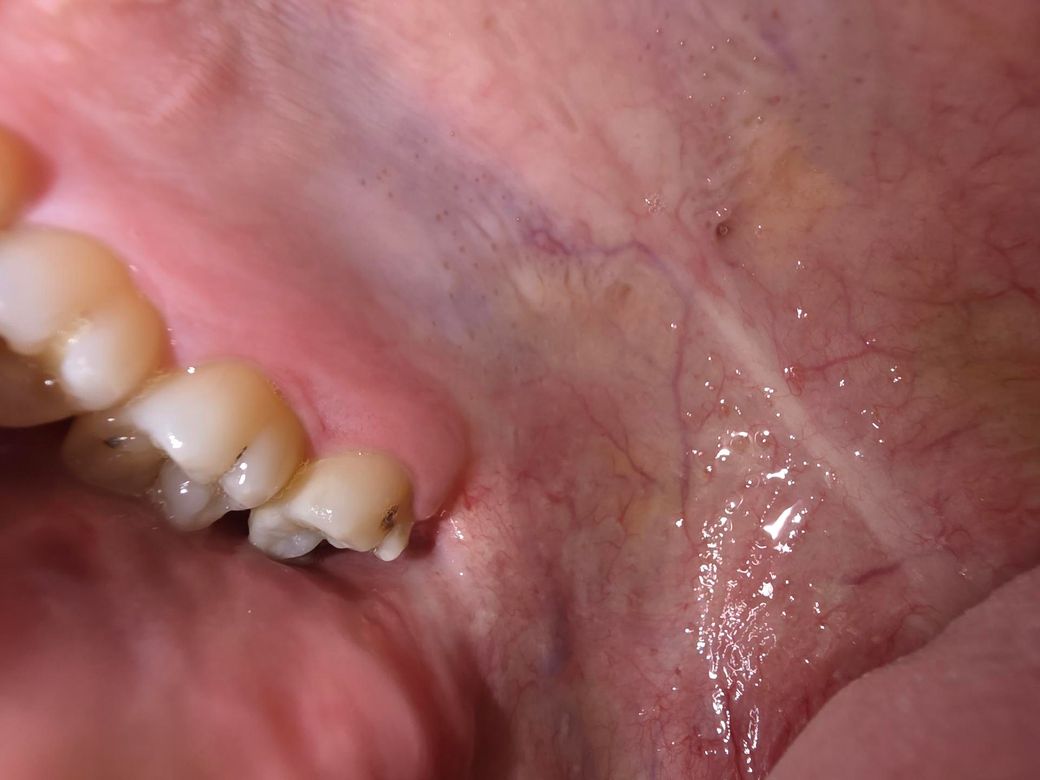

충치 발치해야할정도인가요? 충치가 너무 많이 진행됐어요

제가 양치하는 습관을 안들여놔서 이빨에 치석도 있고 충치도많은데요 충치가 있는 상태에서 치과를 안간지 몇년이 됐더니 맨끝 어금니를 혀로 훑었을때 되게 파여있고 그 이빨에 음식물이 엄청 껴요 딱히 통증이 있거나 하진않은데 발치해야할 정도인가요?

• 2번 째 사진

사진으로 봤을 경우에는 충치가 깊은것으로 보이지는 않습니다.

하지만 정확한확인을 위해서는 치과에서 진료를 받아 보는것이 좋습니다.

발치해야할 정도는 아닐 것 같습니다 보통 충치 때문에 발치를 해야할 정도라면 치아가 거의 다 날라간 정도입니다